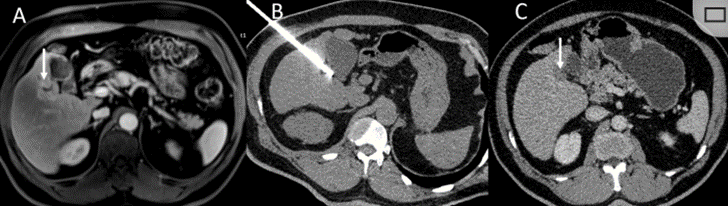

冷凍消融膽囊附近腫瘤病灶

(A)動脈期 MRI 顯示膽囊附近有外周增強(qiáng)病變(箭頭)。

(B)手術(shù)過程中 CT 顯示冷凍探針位于病灶內(nèi)。

(C)消融后,術(shù)后 1 個(gè)月CT 顯示完全消融(箭頭)。